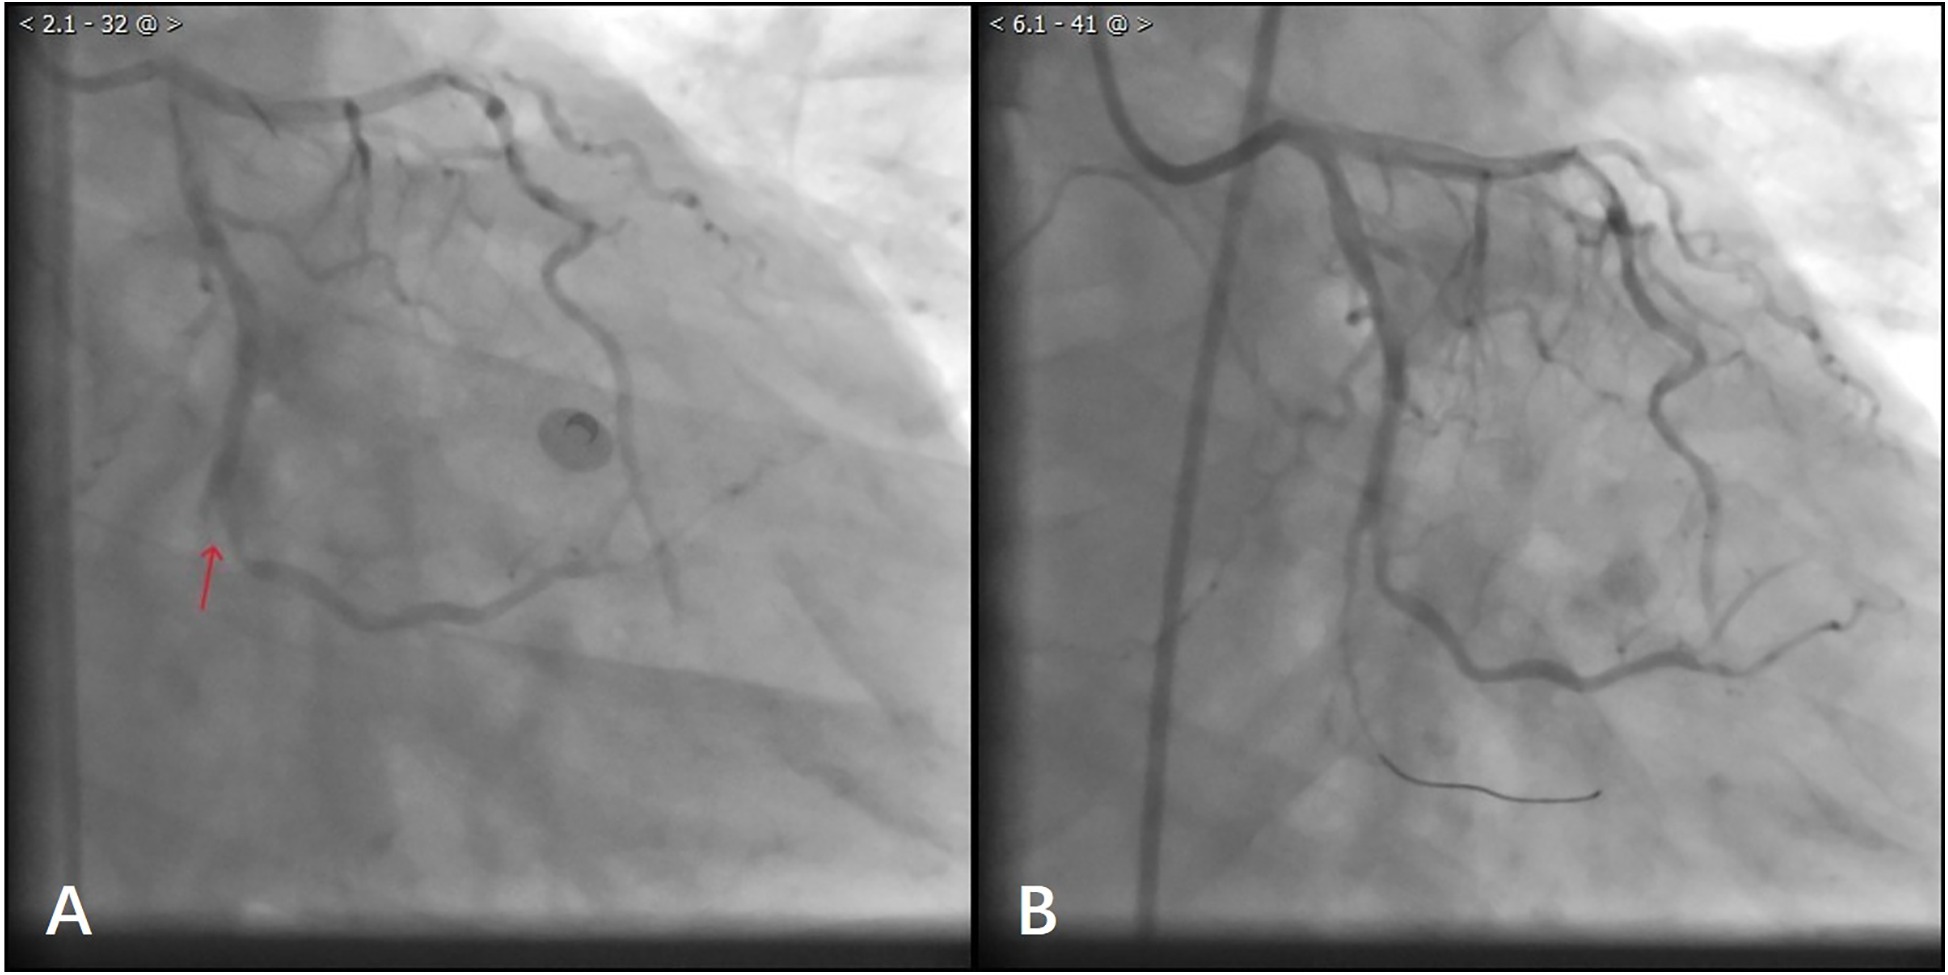

After waiting for 10 min, the laboratory results showed TroponinI 0.87 ng/ml (0.01–0.023), D-dimer: 978 ng/ml (80–500), N-Terminal Pro-Brain Natriuretic Peptide 599 ng/L (300–500), Lactate 25 mmol/L (0.5–1.6), Glucose 30 mmol/L (3.9–5.8), Potassium 2.7 mmol/L (3.4–4.5). Considering that the patient's troponin was markedly elevated and his D-dimer was not, the decision was made to proceed with coronary arteriography. The coronary angiography of the patient showed normal left coronary artery opening and main body; more than 70% systolic stenosis in the middle muscular bridge of the left anterior descending branch, about 50% stenosis in the middle of the diagonal branch, TIMI flow grade 3; normal opening of the left coronary artery circumflex, no obvious stenosis in the main body, distal occlusion, TIMI flow grade 0; normal opening of the right coronary artery, 30%–40% stenosis in the middle, TIMI flow grade 3 (Figure 2A). During the operation, the patient's blood pressure decreased, and we gave fluid replacement and continuous noninvasive ventilator-assisted breathing. The vessels in the distal segment of the occluded circumflex were small (Figure 2A), which was inconsistent with the clinical manifestations of critical illness. Considering the possibility of aortic dissection, an urgent aortic CTA was performed.

Figure 2

(A) Patient with angiographic occlusion of vessels distal to the gyratory branch. (B) Blood flow through the distal vessels of the gyratory branch after balloon dilatation.

During this period, although the patient underwent echocardiography, the bedside ultrasound did not find pericardial tamponade, but only moderate amount of pericardial effusion due to the patient's obesity, restlessness and the limitations of the ultrasound operator's level. Subsequent aortic CTA revealed a significant volume of pericardial effusion without evidence of aortic dissection. The clinical manifestations were initially attributed to the combined effects of pericardial effusion and coronary pathology. To further clarify the cause of death, a senior radiologist meticulously reviewed the imaging studies and identified contrast medium extravasation from the myocardium into the pericardial cavity (Figure 3). After aortic dissection was ruled out, the patient was returned to the cath lab for further treatment of distal circumflex branch occlusion and pericardiocentesis. Procedure: The guide wire was sent through the catheter and passed through the distal end of the circumflex branch occlusion segment successfully. Blood flow passed through the circumflex branch occlusion segment after balloon expansion. The TIMI grade was 3 (Figure 2B). Unfortunately, pericardiocentesis under DSA guidance was not successful.

Early diagnosis and timely emergency surgical treatment of such patients can be expected to be successful. Given its convenience and rapid availability, echocardiography remains recognized as the first-line diagnostic modality for cardiac rupture (11, 12). Although echocardiography demonstrates moderate sensitivity (70%) and high specificity (90%) in detecting cardiac rupture, its diagnostic accuracy heavily depends on operator expertise and patient cooperation (13), which can be particularly challenging in critically ill patients. Therefore, when echocardiography fails to provide a definitive diagnosis, supplementary imaging modalities should be considered. In our case, no extravasation of contrast media was found in the patient during coronary angiography, but the clinical manifestations were inconsistent with coronary vascular disease. However, in order to rule out aortic dissection, we performed an aortic CTA examination and observed contrast agent shuttling through the myocardium and reaching the pericardium, definitively diagnosing the patient's heart rupture diagnosis.